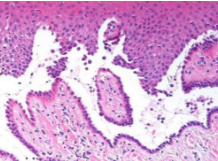

Histopathology

Rounded, acantholytic epithelial cells sitting within the intraepithelial cleft

The basal cells are attached to the basement membrane "row of tombstones"

Diagnosis should be confirmed by direct immunofluorescence studies (antibodies against desmosomes)

Histopathology:

Mucous membrane pemphigoid showing characteristic subepithelial separation (antibodies directed against basement membrane proteins)